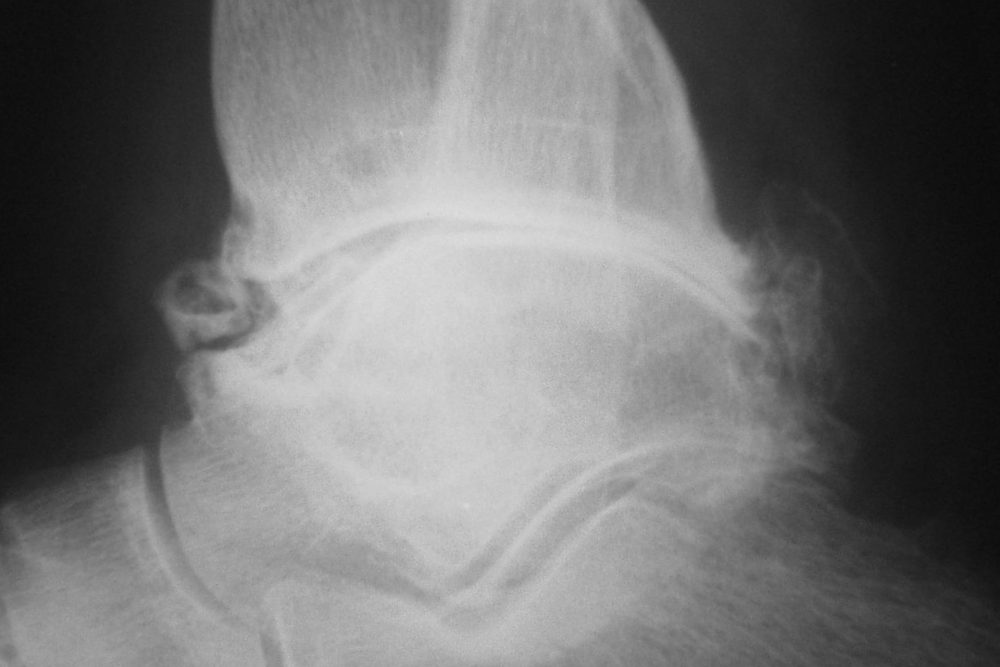

Osteoarthritis in the ankle and foot Buxton Osteopathy Clinic Arthritis In Foot Ball Joint Arthritis will cause the joints to wear. This leads to joint pain and. The major types of arthritis that affect the foot and ankle are osteoarthritis, rheumatoid arthritis, and posttraumatic arthritis. — osteoarthritis (oa) is a chronic condition that causes the cartilage in a person’s joints to deteriorate gradually. — many different kinds of arthritis can affect different. Arthritis In Foot Ball Joint.

Talonavicular Arthitis Arthritis Of The Talonavicular Joint Arthritis In Foot Ball Joint — arthritis can affect one or more of the joints of your foot. The major types of arthritis that affect the foot and ankle are osteoarthritis, rheumatoid arthritis, and posttraumatic arthritis. Foot arthritis causes pain, stiffness, and swelling that can reduce mobility and quality of life. — osteoarthritis (oa) is a chronic condition that causes the cartilage in. Arthritis In Foot Ball Joint.